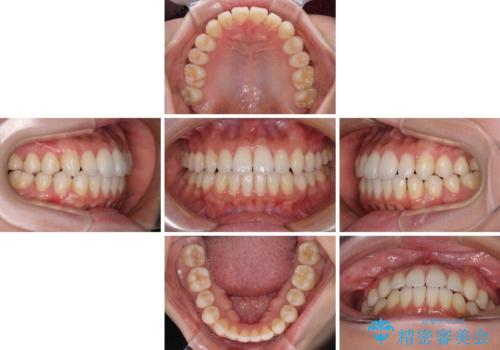

- 下唇に上の前歯が当たることを気にして来院された患者様です。

上顎の親知らずを抜去し、歯列全体を後方に移動させるとともに、IPR(歯と歯の間を削る)を行うことで口元の閉じにくさを改善していくこととしました。

咬合力が強く、マウスピースを介した咬み込みが顕著であったため、奥歯の咬みにくさやIPRのスペースが改善しにくく、治療期間が思った以上にかかってしまいました。